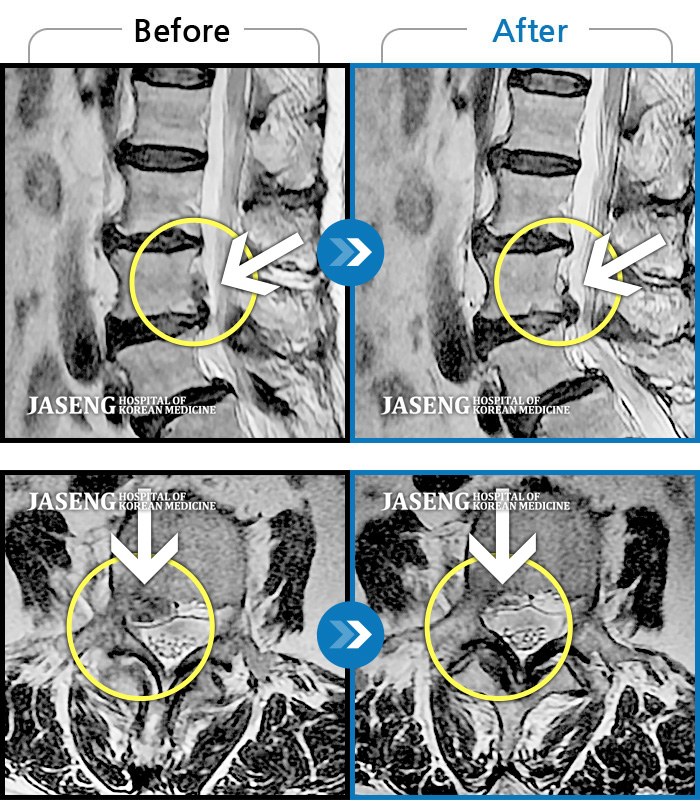

Before

After

환자에게 사전 동의를 받아 동일 조건에서 촬영되었습니다.

개인에 따라 치료 후 부작용이 발생할 수 있으니 의료진과 상담 후 치료를 진행하시기 바랍니다.

일상생활 불가능한 통증으로 본원에 입원 위해 내원

목, 왼쪽 어깨에서 왼쪽 팔까지 아파요.